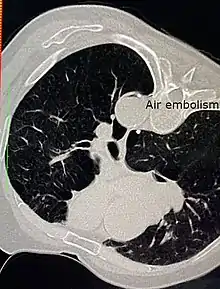

Air embolism

An air embolism, also known as a gas embolism, is a blood vessel blockage caused by one or more bubbles of air or other gas in the circulatory system.[1] Air can be introduced into the circulation during surgical procedures, lung over-expansion injury, decompression, and a few other causes. In flora, air embolisms may also occur in the xylem of vascular plants, especially when suffering from water stress.[2]